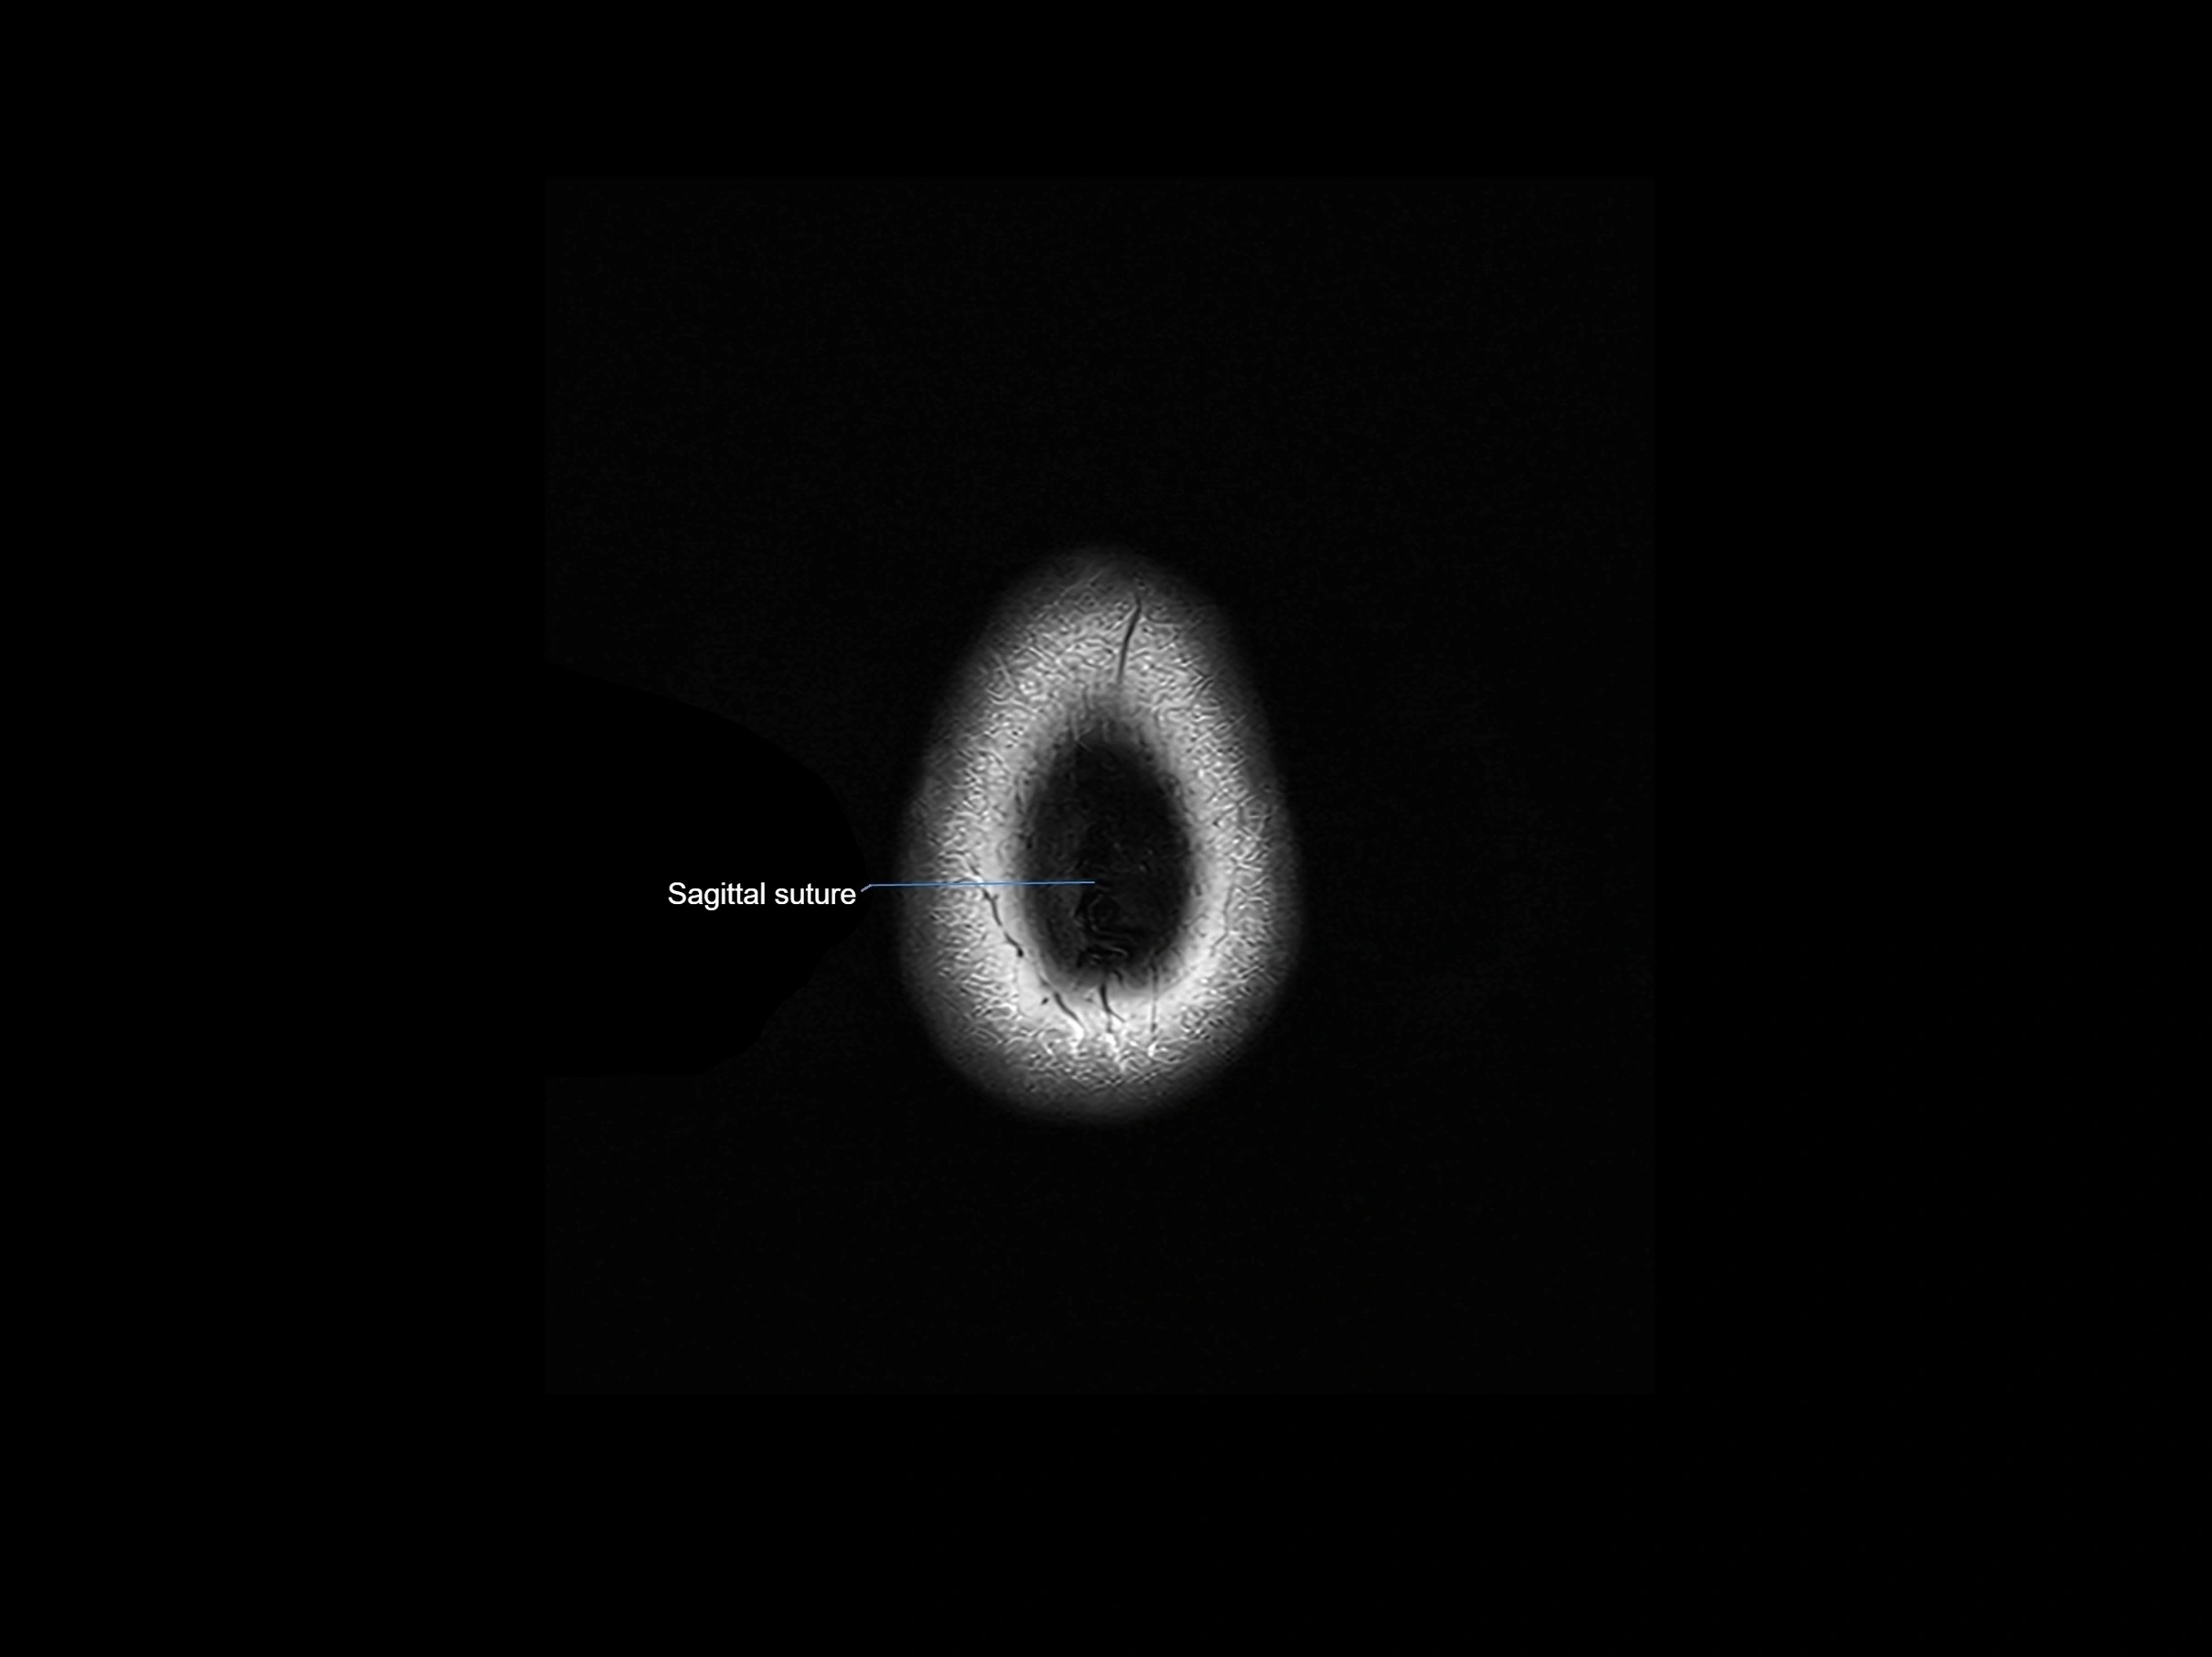

- Sagittal suture